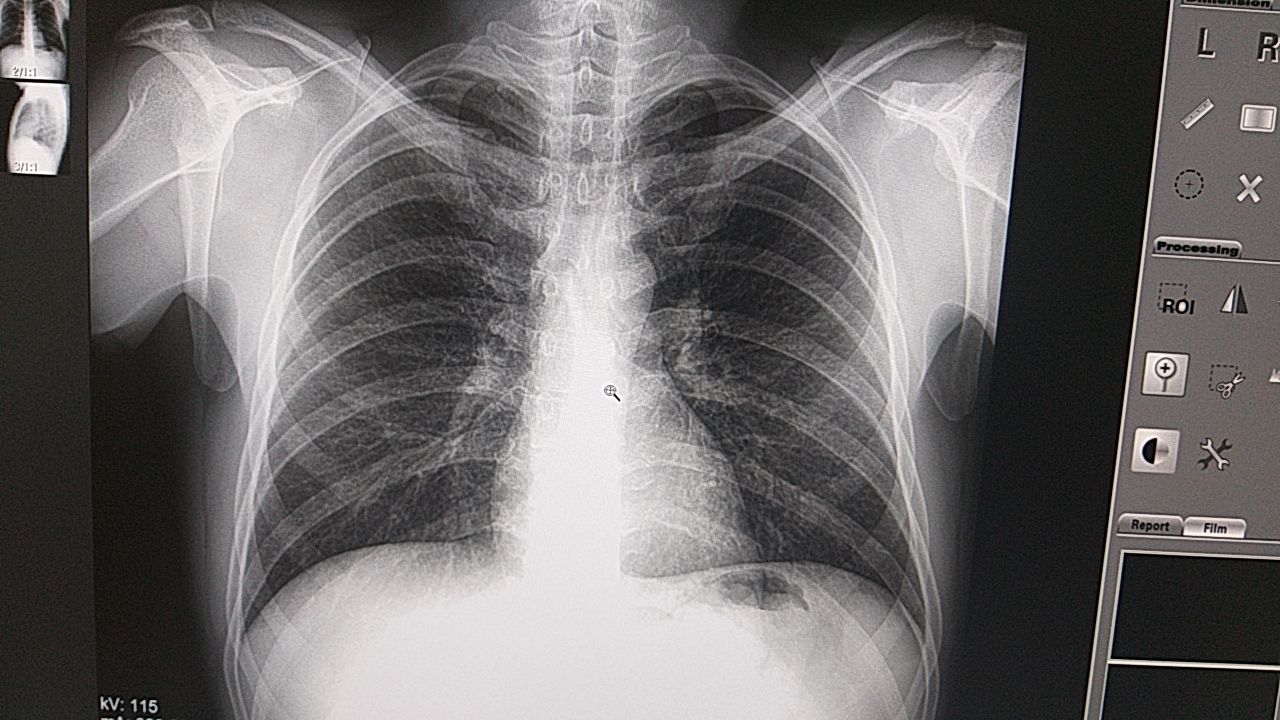

Или фиброзные изменения в.д s 3

Это что за снимок

Это не вчерашний

Не похож

Это другой снимок ты что путаешь на счёт фиброза